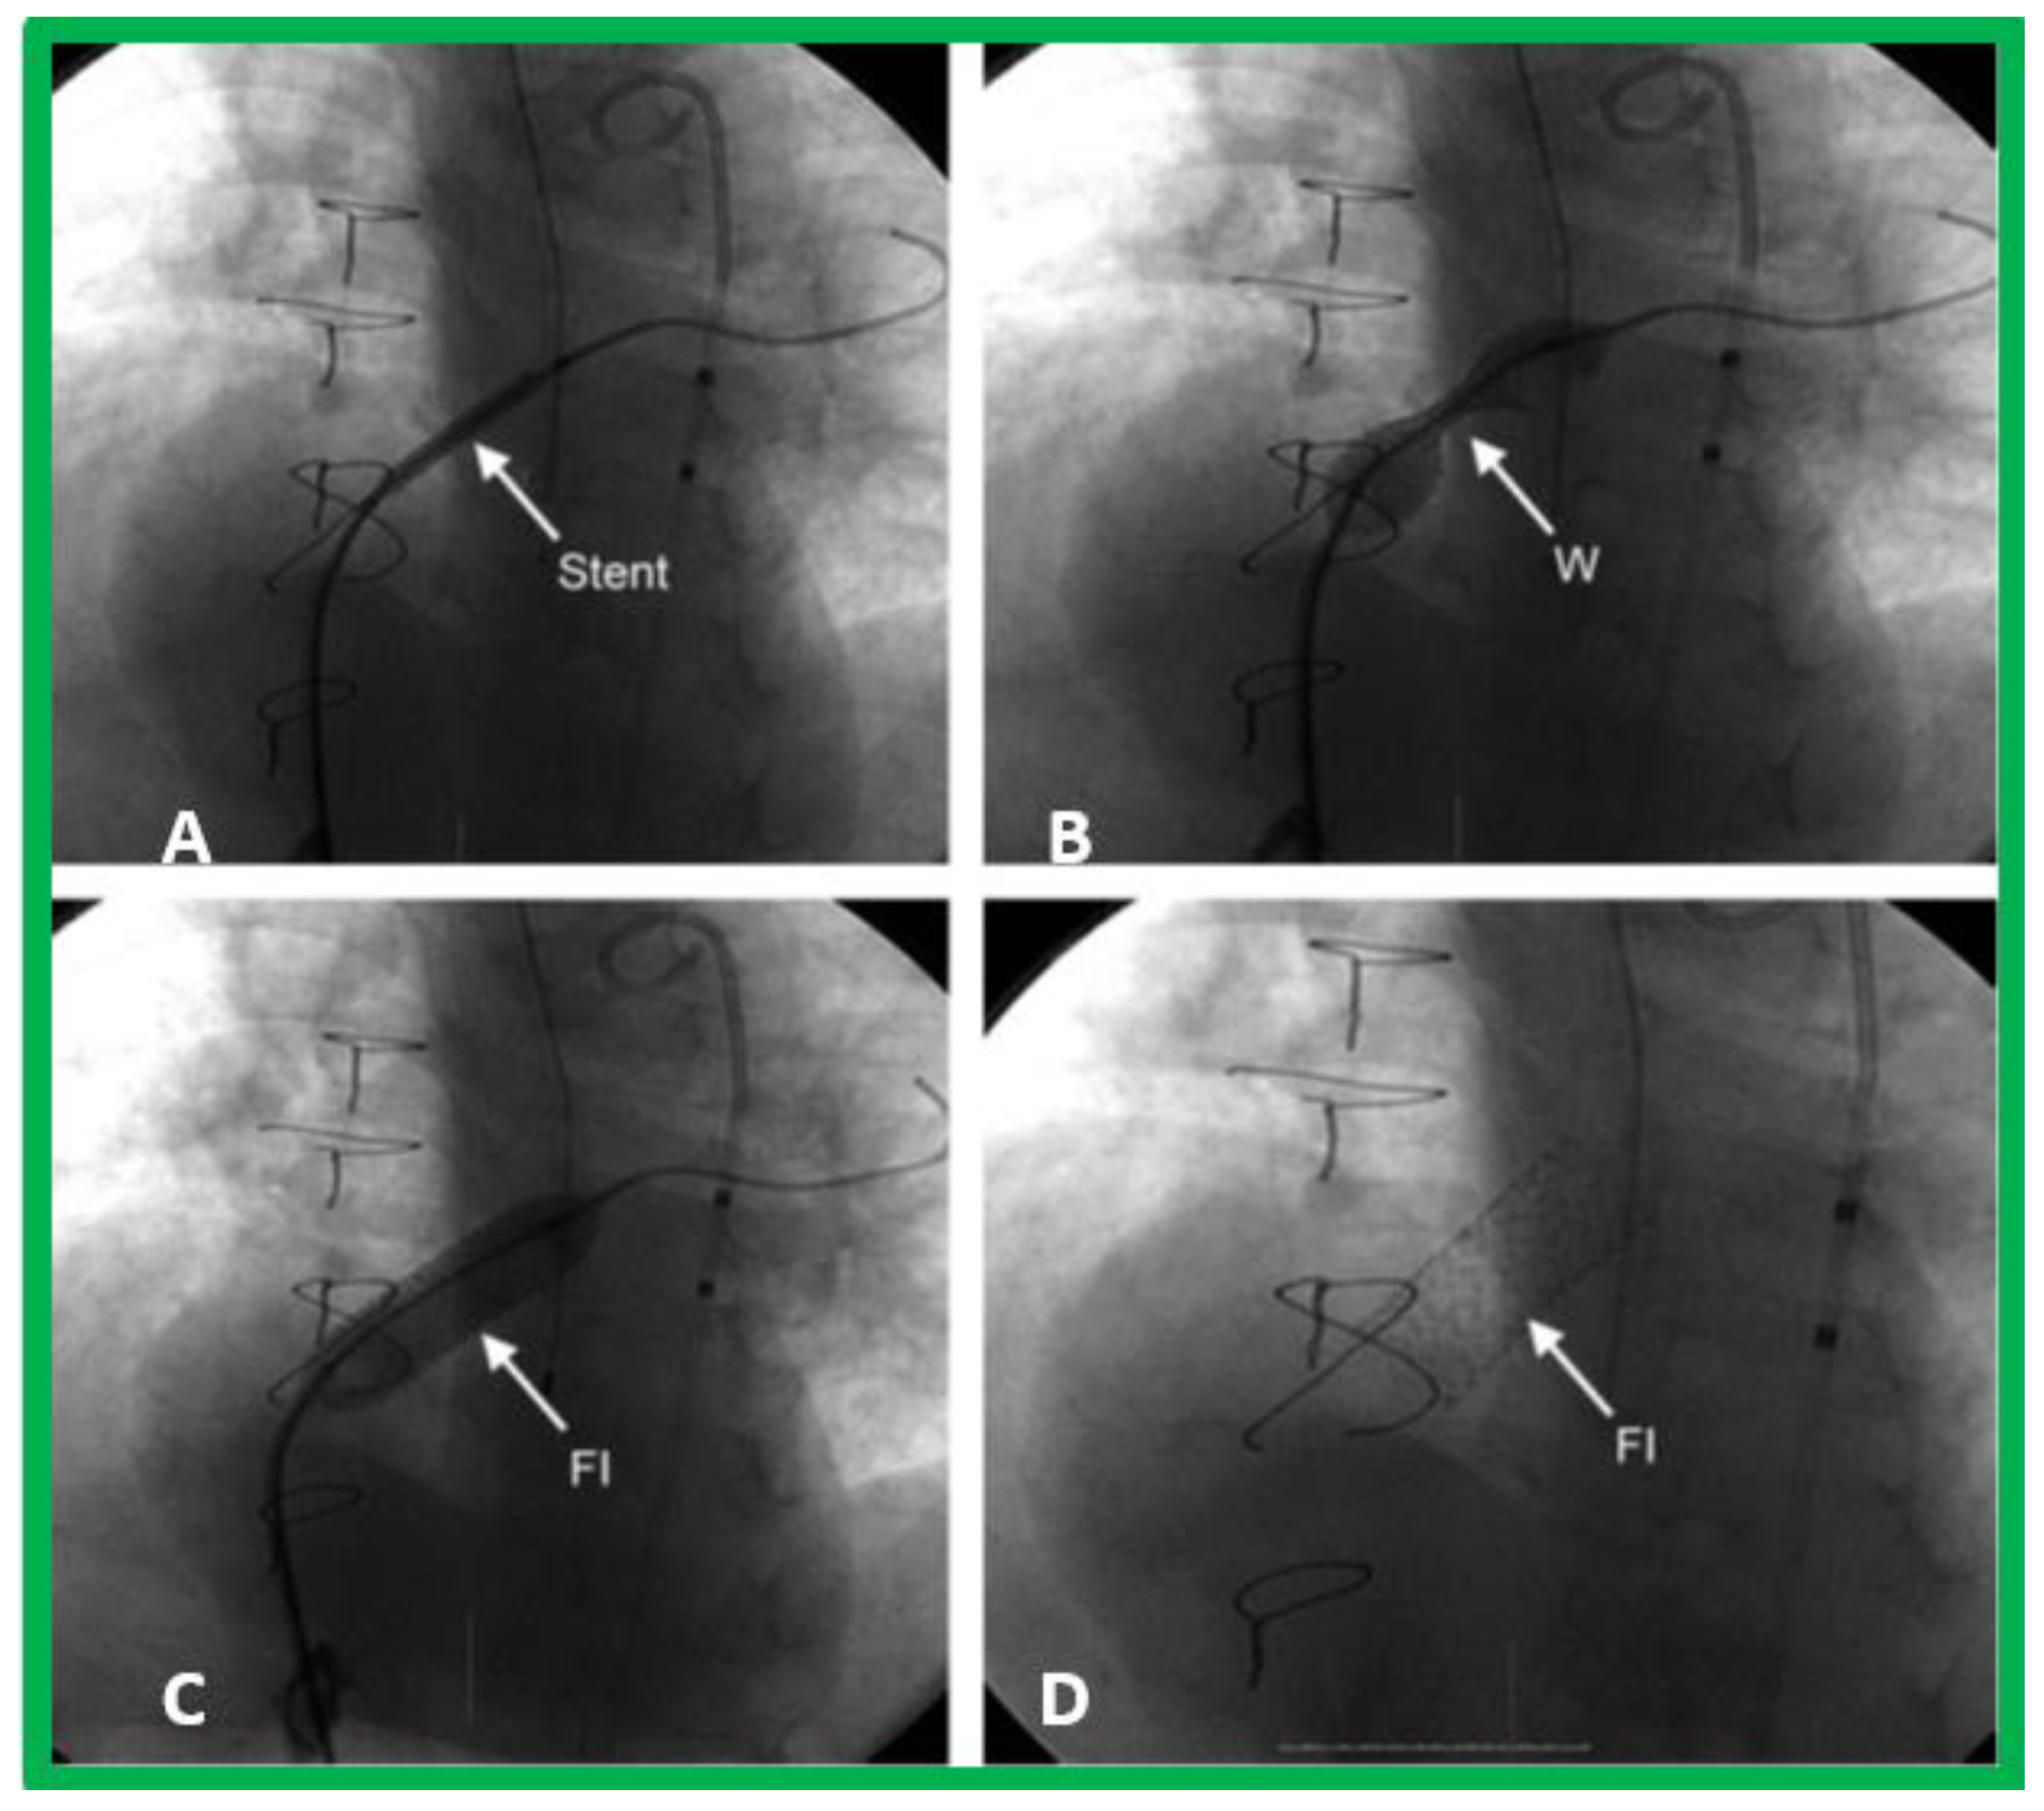

10. Therapy

10.1. Therapy at Initial Presentation

10.1.1. Inter-Atrial Obstruction

10.1.2. Decreased Pulmonary Blood Flow

10.2. Follow-Up after Initial Palliation